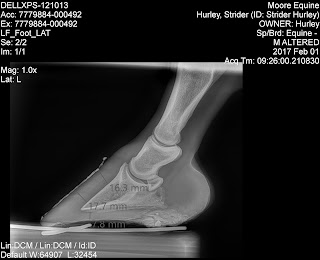

Here they are.

As noted, on his right front, we have 8.5mm and on the left front we have 7.8mm. Just barely over half of what the vet thinks is ideal.

Yes, those toes are long. In my farrier's and my defense, he was trimmed on 1/1/17 so you're looking at about 4.5 weeks of growth. It very much needs to be pushed back. And, once I get the shoer out *gulp*, that is what we will be doing.

The vet said that for endurance horses, he likes a sole depth of (either) 13 or 14. Strider was at 7.8 on one foot and at 8.something on the other. Or, as the vet put it, "He just sheds it faster than he can grow it."